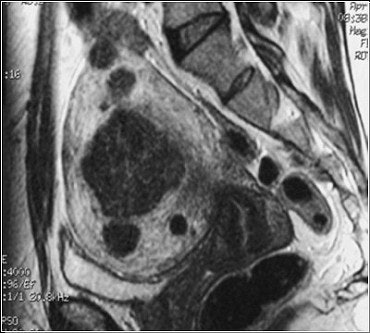

![]() |

| This pre-embolization, sagittal T1-weighted midline MR depicts an enlarged uterus with multiple fibroids highlighted by white arrows. The black arrow points out the uterus impinging anteriorly on the bladder neck. Image courtesy of Dr. Steven Janney Smith. |